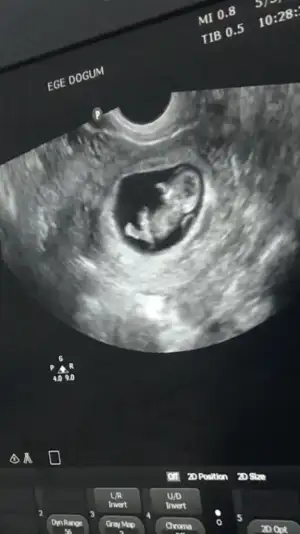

9+6 haftalığız burada sizce kızlar 🥰

18,5 KB · Görüntüleme: 99